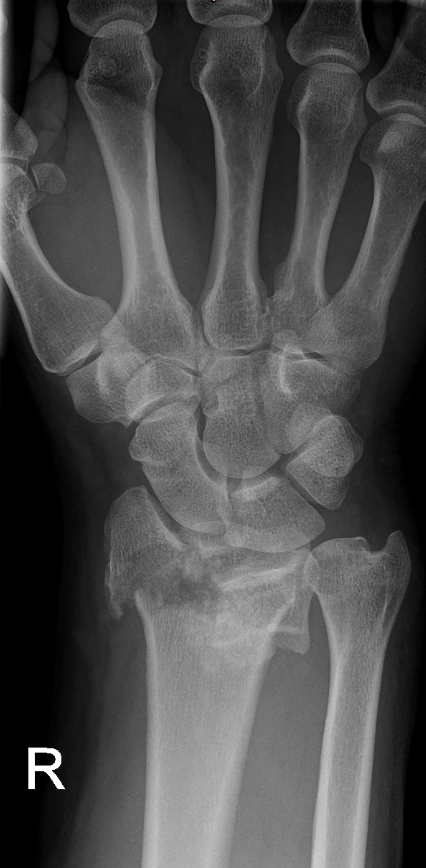

Interposition of the index flexor digitorum superficialis tendon beneath a fragment of the distal radius fracture: a case report

High-energy distal radius fractures are characterized by significant displacement of bone fragments, articular surface damage, and ligamentous injury. Tendon interposition between bone fragments occurs very rarely. In this report, we present a case of a complex distal radius fracture in which intraoperative findings revealed interposition of the flexor digitorum superficialis tendon of the index finger beneath one of the fracture fragments. The exceptional rarity of this situation prompted the authors to report this case.